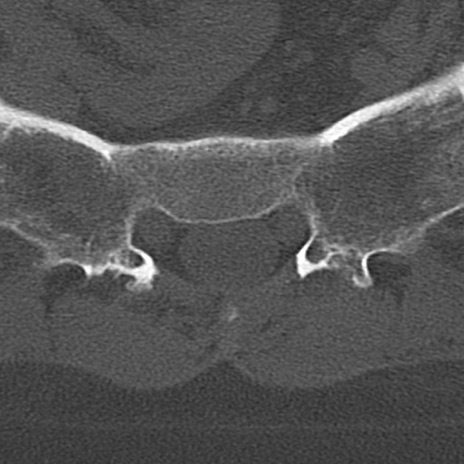

腰椎CT

冠状断像